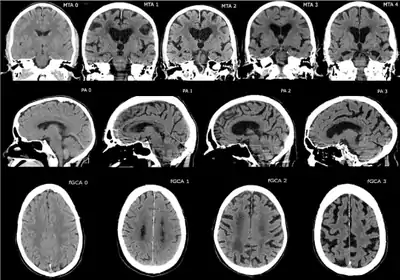

CT and MRI are most commonly used to observe the brain for cerebral atrophy. A CT scan takes cross sectional images of the brain using X-rays, while an MRI uses a magnetic field. With both measures, multiple images can be compared to see if there is a loss in brain volume over time.[12]